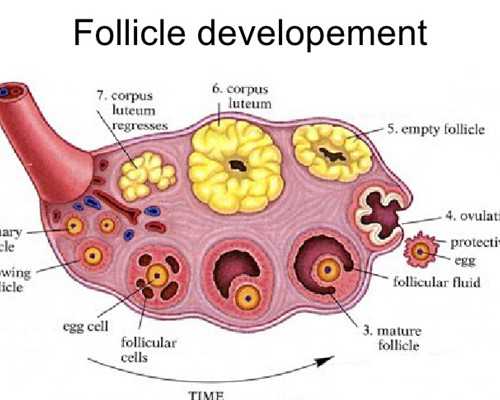

捐卵試管技術(shù):一代捐卵、二代捐卵

卵源等待時(shí)間:該院區(qū)卵源等待時(shí)間至少一年半起

2023煙臺(tái)市可開(kāi)展捐卵試管嬰兒技術(shù)的醫(yī)院共有2家,且均可開(kāi)展一代捐卵和二代捐卵試管技術(shù),不孕患者是可以將這2家醫(yī)院納入考慮范圍的。